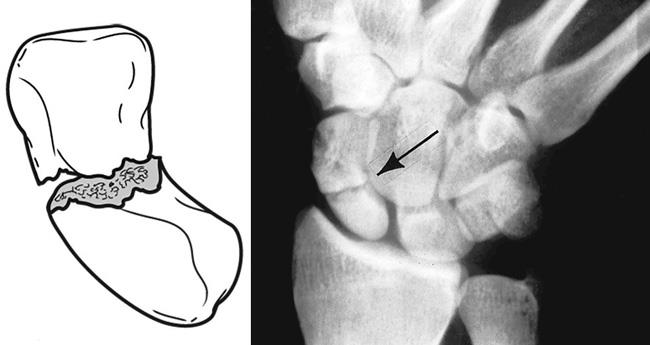

분류는 Herbert Classification 을 통해 분류할 수 있습니다.

A부터 D 타입으로 나눌 수 가 있는데

A의 경우 급성 안정골절, B의 경우 급성 불안전 골절, C의 경우 지연유합, D의 경우 불유합 으로 나뉠 수 있습니다.

불안정한 급성골절인 B의 경우 수술적 치료가 필요한 경우가 많기 때문에 주의깊게 보아야 합니다.

불안정과 전위를 나누는 기준은 다음과 같습니다.

(1) 골절 조각의 범위가 1mm 이상 늘어난 경우 (전후면이나 사선 엑스레이에서)

(2) Lunocapitate 각이 15도 이상인 경우(측면)

(3) Scapholunate 각이 45도 이상인 경우 (측면)

(4) Intrascaphoid 각이 45도 이상인 경우 (측면) or 35도 이하인 경우(전후면)

(5) height-to-length 비율이 0.65 이상인 경우